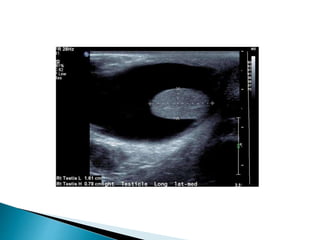

Ultrasound first line investigation

 Located within inguinal canal

 May be normal or atrophic

MRI if not found high signal on T2 and STIR

Ultrasound first lineinvestigation  Located within inguinal canal  May be normal or atrophic MRI if not found high signal on T2 and STIR  Testicular phlebography or arteriography